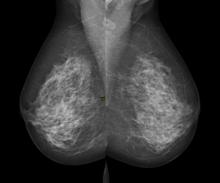

Revisiting the Impact of Breast Density on Diagnosing Breast Cancer

By Chuck Dinerstein, MD, MBA — Jun 27, 2018

Breast cancer is more difficult to detect in women whose breasts are dense. It is unclear whether there is also underlying behavioral differences in their cancers. Should we treat them as a separate population?